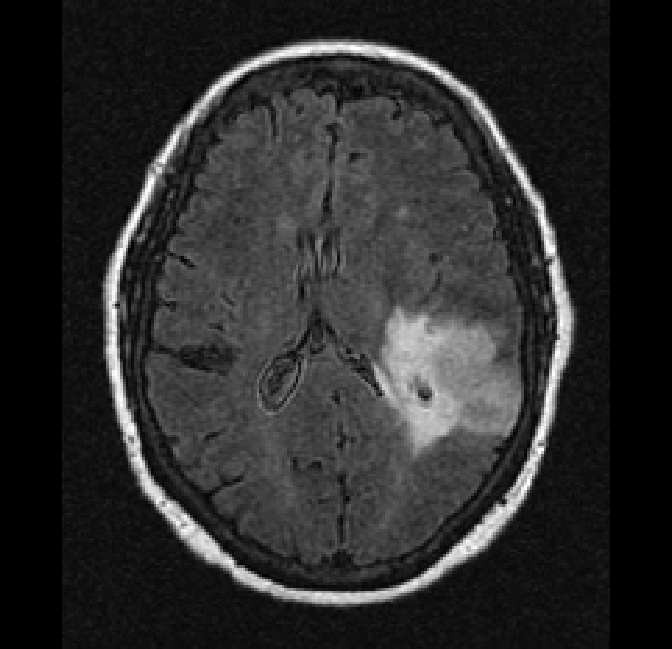

By not excluding scans from our train set based on radiological characteristics, we were able to make our model robust to low scan quality, as can be seen in an example from the test set in Figure 7. Even though this example scan contained imaging artifacts, our method was able to properly segment the tumor (DICE score of 0.87), and correctly predict the tumor as an IDH wildtype, grade IV tumor.